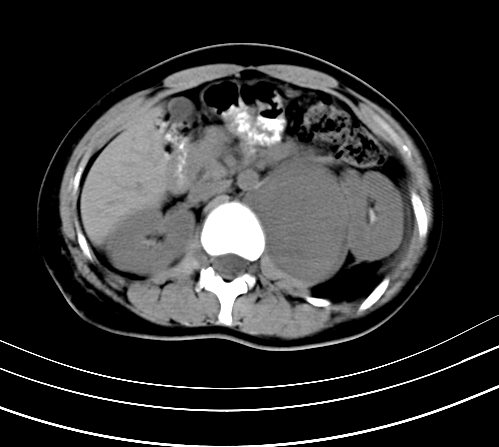

腹部平扫